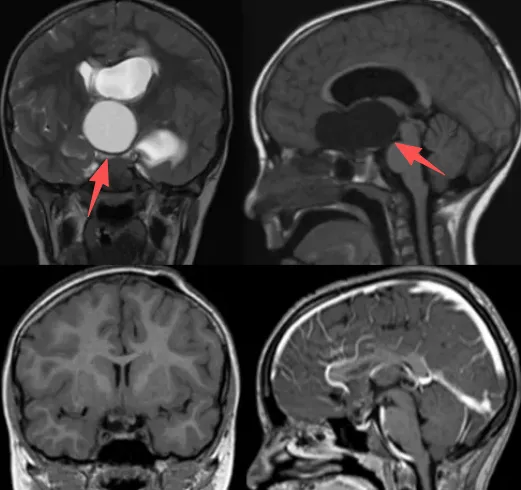

手术治疗是医生建议的主要方案,但患儿家属并未立即接受,而是寻求多家医疗机构的诊疗意见。最终,家属带患者咨询Rutka教授。教授评估认为,由于肿瘤属囊性颅咽管瘤,可尝试采用囊肿分流术替代传统开颅手术以达到肿瘤减容目的。

家属接受该治疗方案后,医疗团队通过植入VP分流器和Ommaya囊实施治疗。在反复按压Ommaya储液囊后,影像学检查显示肿瘤体积明显缩小,几乎达到完全消失的效果。

Rutka教授在2022年发表的研究指出,采用大面积切除手术或放疗治疗儿童颅咽管瘤可能导致严重并发症。将Ommaya储液囊植入囊性颅咽管瘤是一种微创手术方式,具有并发症发生率低、可即时减压、避免额外损伤等优势,并能有效保留患儿内分泌功能。

该病例证实,对于特定类型的囊性颅咽管瘤,采用Ommaya囊技术可避免传统开颅手术带来的创伤,同时取得良好的肿瘤控制效果。这种微创治疗方法为儿童颅咽管瘤的治疗提供了新的选择,特别适用于无法耐受或不愿接受传统开颅手术的病例。